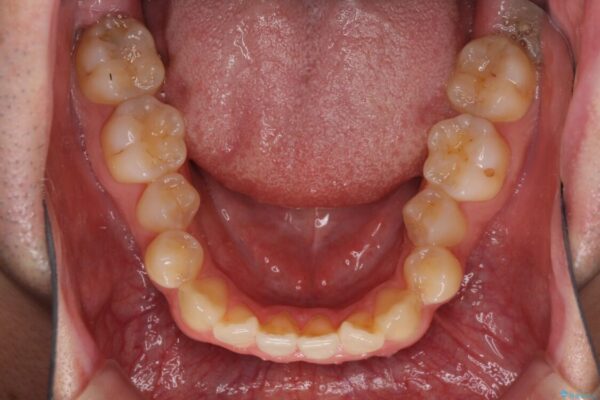

治療前

• 左右の八重歯が気になる ワイヤー装置での咬み合わせ改善 治療前画像